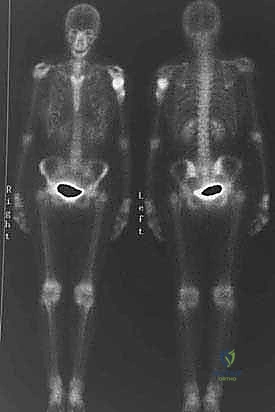

* Technetium Tc 99m Bone Scan: Confirmed an isolated humeral lesion, ruling out skip lesions or polyostotic disease, which is essential for staging and ensuring we're not missing multicentric disease.